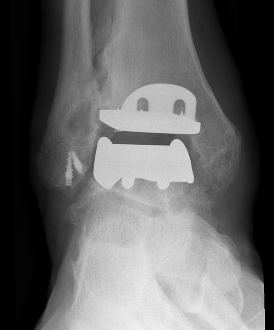

Infinity implant STAR implant Inbone

Agility Salto Tolaris Trabecular metal